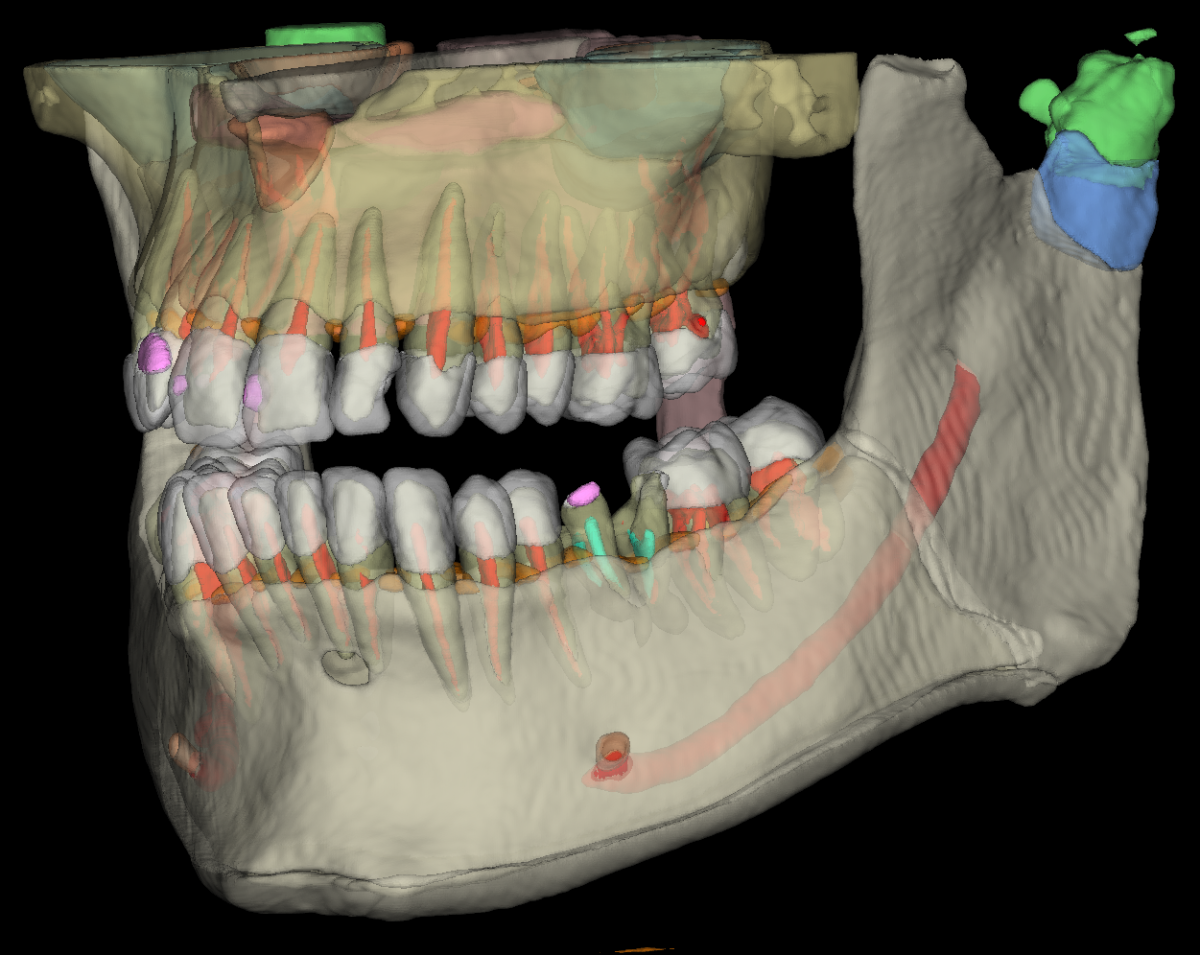

3D snimanje zuba (Cone Beam Computed Tomography) je revolucija u stomatološkoj radiologiji. Za razliku od klasičnog 2D ortopana, 3D snimak generiše trodimenzionalni model zuba, vilica, sinusa i koštanih struktura.

- Endodoncija (3D ENDO): Precizna analiza kanala korena i upalnih procesa.

- Oralna hirurgija: Bezbedne operacije zuba i vilica.

- Ortodoncija: Detaljan prikaz odnosa vilica i položaja zuba.

- Sinusi i zglobovi: Analiza maksilarnih sinusa i viličnog zgloba (TMZ).